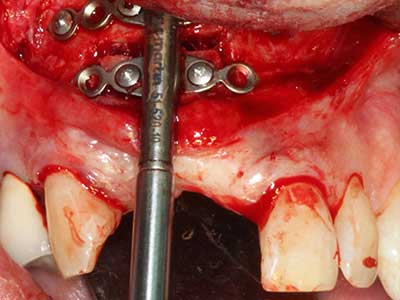

Quando le procedure chirurgiche vengono eseguite sull'osso nelle immediate vicinanze di strutture sensibili, come vasi sanguigni o nervi, gli strumenti rotanti pongono un rischio significativo di lesione iatrogena. I dispositivi piezoelettrici possono essere utili per la preparazione delle coperture ossee e la rimozione del tessuto duro in prossimità dei nervi, in particolare per la loro esposizione dopo una lesione iatrogena, ma anche durante la lateralizzazione dei nervi per le procedure di resezione e ricostruzione o il posizionamento di impianti (figg. 17-20). Il contatto leggero tra puntina piezoelettrica e nervo non causa generalmente danni, ma se si procede senza prestare attenzione con movimenti a sega o raccordi con residui di substrati ossei possono verificarsi danni al nervo temporanei o anche permanenti. Il rischio di danno, tuttavia, è considerato sostanzialmente inferiore al rischio presente utilizzando seghe o frese (Pereira, Gealh et al. 2014).

Fig. 18: preparazione di una copertura corticale con sega piezoelettrica per osso (Piezomed, W&H).

Fig. 19: sito chirurgico dopo neurolisi e rimozione dell'osteoma.

Fig. 20: la copertura ossea rimossa viene riadattata e fissata con una vite per osteosintesi (KLS Martin, Tuttlingen).